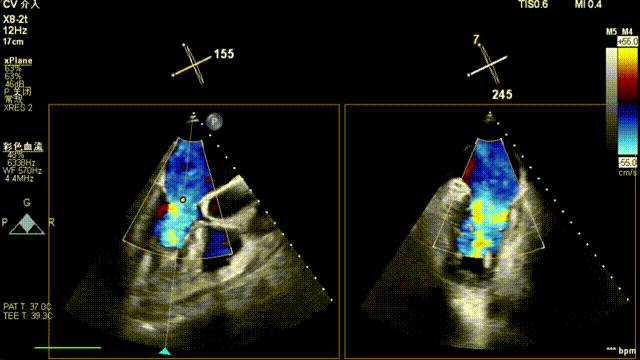

患者为原发性二尖瓣反流(DMR),收缩期可见二尖瓣反流信号,反流位于 2 偏 3 区,基线期二尖瓣反流程度4+。

前叶长度 15.7mm,后叶长度 12.7mm,后叶脱垂宽度13.9mm,脱垂高度4.76mm, 瓣环直径37.1mm,VC:4*7mm, MVA约4cm² 。瓣叶质地较差,腱索断裂、后瓣叶脱垂。

术前超声